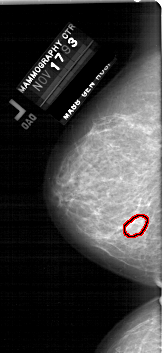

A_1915_1.LEFT_MLO

LEFT_MLO LINES 6316 PIXELS_PER_LINE 3076 BITS_PER_PIXEL 12 RESOLUTION 43.5 OVERLAY

FILE: A_1915_1.LEFT_MLO.OVERLAY

TOTAL_ABNORMALITIES 1

ABNORMALITY 1

LESION_TYPE MASS SHAPE OVAL MARGINS OBSCURED

ASSESSMENT 3

SUBTLETY 2

PATHOLOGY BENIGN

TOTAL_OUTLINES 1

BOUNDARY